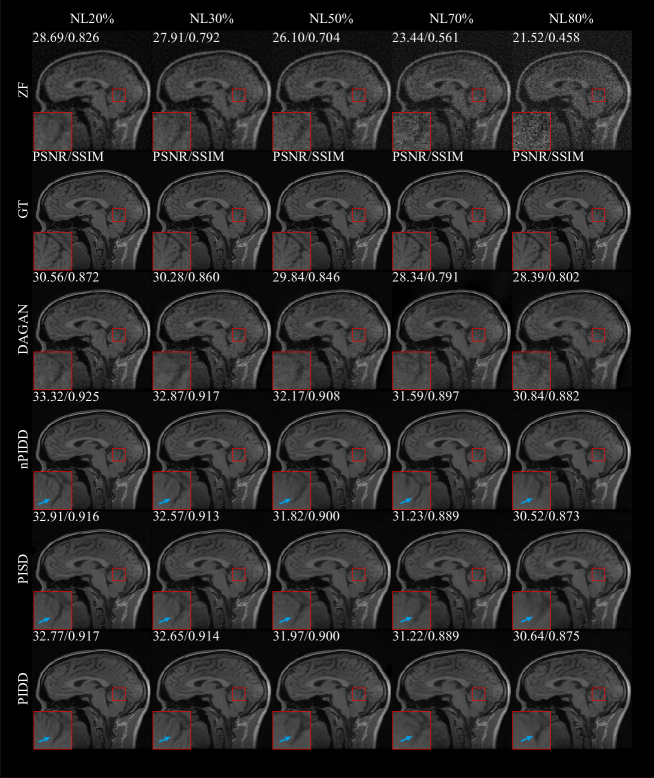

The testing results are shown in Fig. 10, and testing samples are shown in the Fig. 11.

All considered methods can restore image structure and edge information for low and medium noise levels (20–50%), with PIDD having strong advantages over PISD and nPIDD. This advantage weakens as noise level increases, and PISD, which focuses on overall information recovery, performance slightly surpasses PIDD, which focuses more on edge information preservation, for high noise (70–80%).

Refer to caption

Figure 11: Testing examples of the experiment on noise using different noise level.